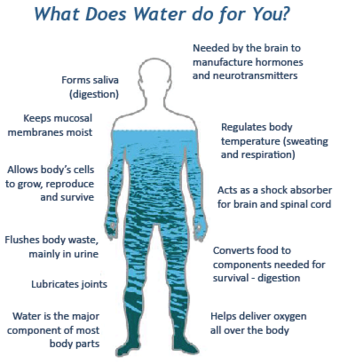

When I directly relate with the intelligence of life, I listen deeply to the body and to nature’s intelligence.

The fascinating revelation is that when I slow down, when I do nothing properly, as in sitting still and simply being, my actions are reflected in my quality of presence. I become far more effective. My psychology and physiology move into symmetry and health.

The key to health is presence. Every therapy and spiritual practice returns us back to the body which only resides in present time.